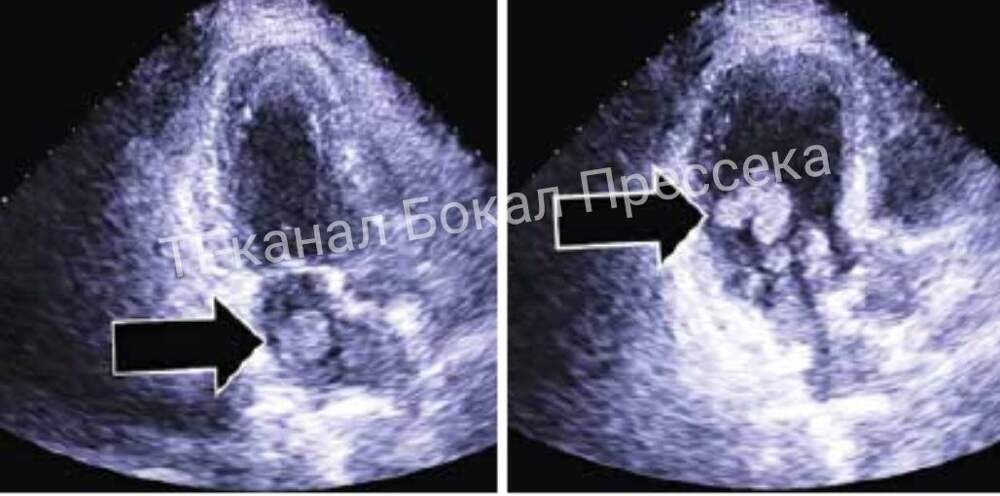

Пациентку удалось спасти благодаря слаженной работе специалистов 13‑й городской клинической больницы и Нижегородского кардиологического центра. Об этом в своем телеграмм-канале рассказал главред ИА «Стационар-Пресс» Алексей Никонов. У женщины была диагностирована миксома — редкая доброкачественная

...Далее